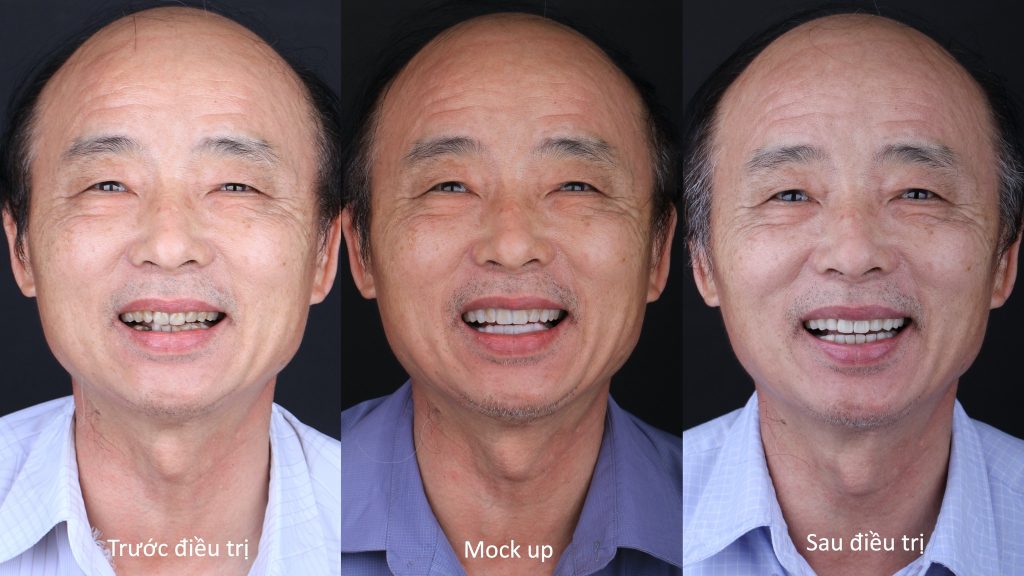

Phục hình hàm cho bệnh nhân 78 tuổi đảm bảo về thẩm mỹ và chức năng